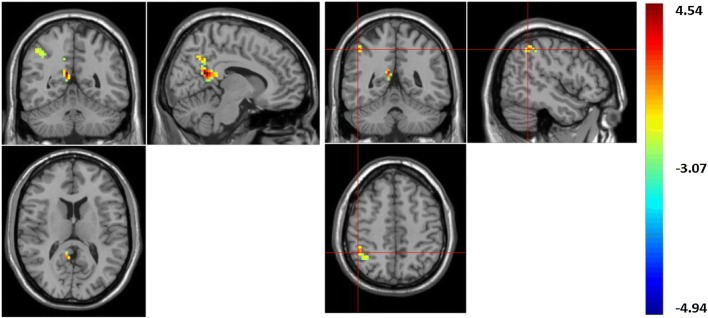

In the current research study, using ReHo values, the boys with LFASD had statistically significantly higher scores than the TD children when it came to the Precuneus (BA 23) and Inferior Parietal Gyrus, IPG (BA 40) (See Fig. 1 and Table 2). At the same time, using ALFF values, the boys with LFASD had statistically significantly higher scores when it came to the Right Middle Temporal Gyrus MTG (BA 21), Angular gyrus (BA 39) and IPG (BA 40) (see Fig. 2 and Table 2).

Fig. 2.

The brain area of increased ALFF value. ALFF value increased in brain areas: right middle temporal gyrus (MTG); right angular gyrus; right inferior parietal gyrus (IPG)